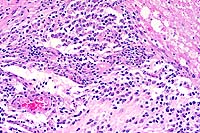

- Case 6-2. Oral mucosa. Beneath the mucosal epithelium

there is a multinodular mass lined by columnar epithelial cells

(arranged in palisades) which surround areas of loose stellate

reticulum. Occasional foci of mineralized debris and squamous

epithelial cells are found within epithelium lined cystic spaces.

- Conference Note: The histomorphology of the tumor

is characterized by islands and anastomosing cords of epithelium

with peripheral palisades of tall columnar cells containing antibasilar

polarized nuclei (preameloblasts) that enclose large, central

areas of stellate reticulum. The columnar cells are separated

from the supportive collagenous stroma by a prominent, brightly

eosinophilic limiting membrane. Multifocally, there are nests

of keratinizing polygonal cells, occasionally containing small

fragments of mineral, which are interpreted as hyperplastic rete

ridges with entrapped epithelium.